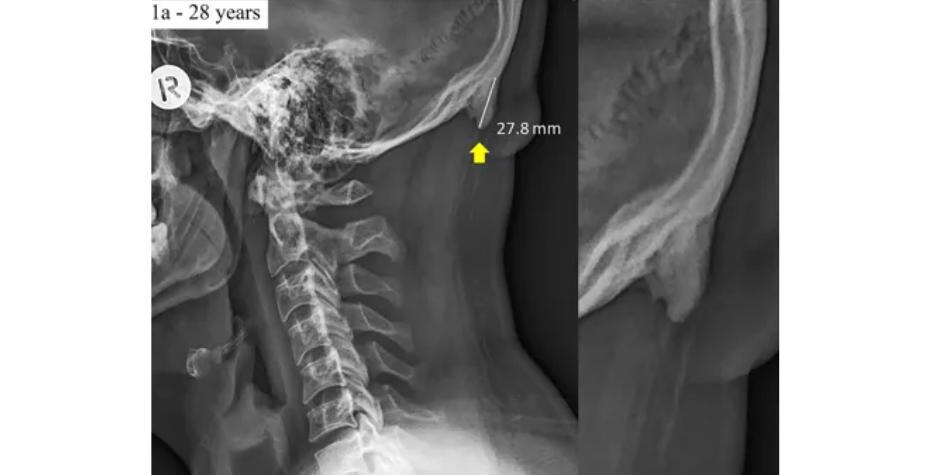

Cases